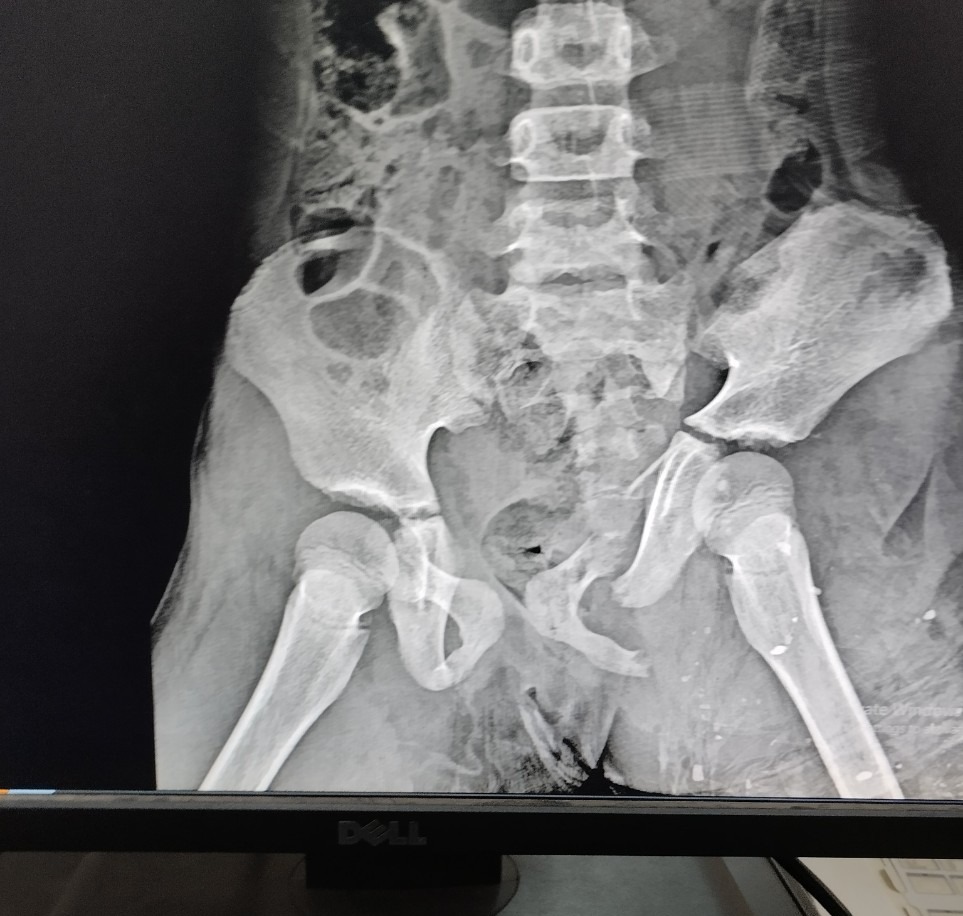

Qua thăm khám bệnh nhân bị rách vùng đùi bên trái, có kích thước 40x15 cm lộ gân cơ, vùng chậu phải có vết rách da 20x7 cm lộ cơ. Bệnh nhân được chỉ định chụp Xquang khung chậu thẳng. Kết quả cho thấy bệnh nhân bị gãy ngành ngồi háng và ngồi mu trái, gãy ngành ngồi mu bên phải. Nhận định tình trạng bệnh nhân nguy kịch, sau khi sơ cứu và hội chẩn kíp trực cấp cứu đã chuyển bệnh nhân lên tuyến trên điều trị tiếp.

Hình ảnh chụp Xquang của bênh nhân